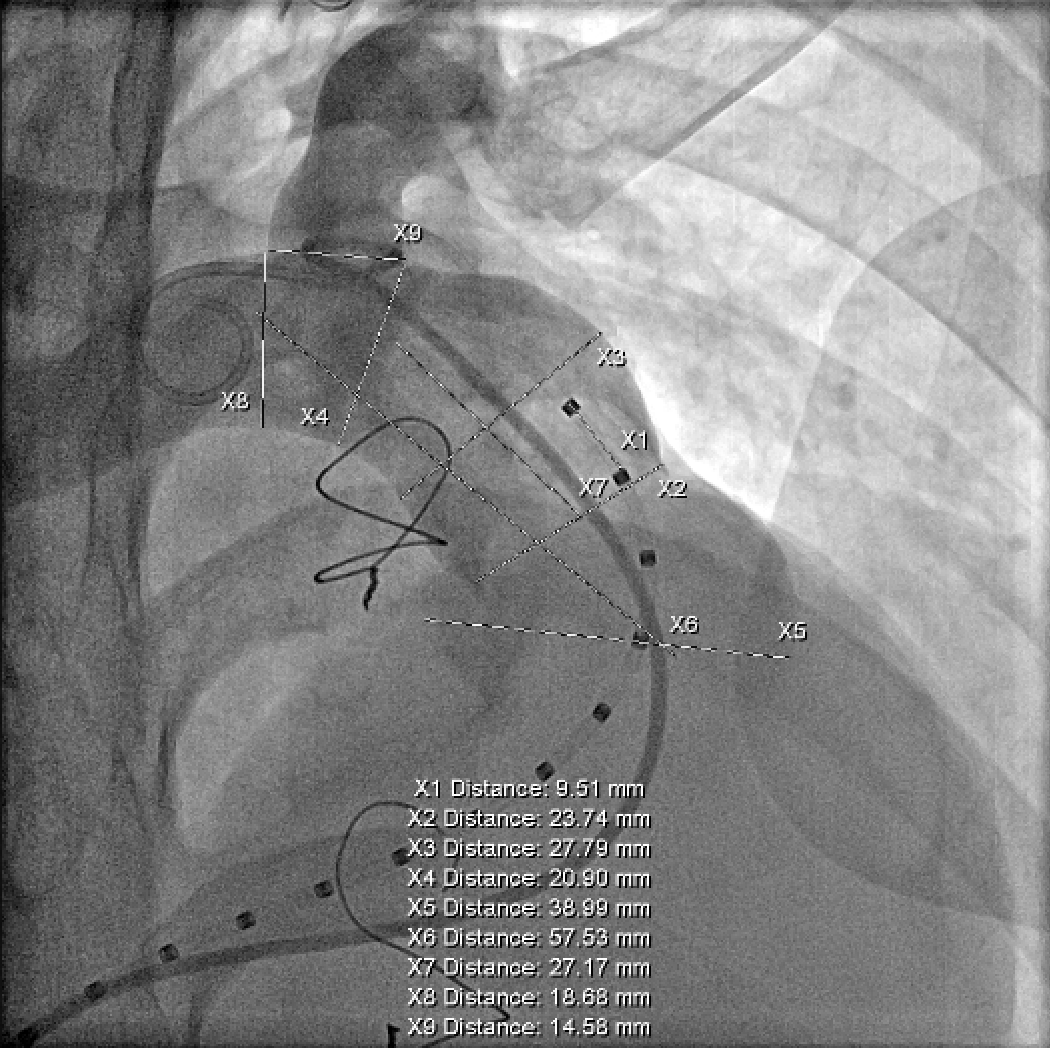

肺动脉造影测量肺动脉内径等参数:

使用顺应性球囊测量肺动脉内径等参数:

根据术前CT、术中造影及球囊测量结果,选择P34-25型号的VenusP-Valve瓣膜,使用圈套器辅助,沿超硬导丝送输送器至肺动脉分叉处。